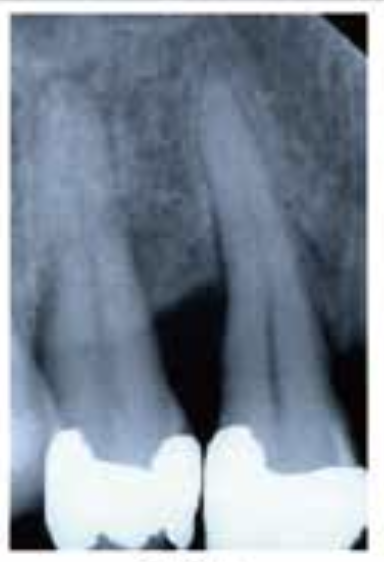

🦷 X-ray 비교

BEFORE

AFTERX-ray 상으로 명확하게 보이는 뼈 재생 효과

1Patient 1: 8년 장기 추적 케이스

치료 시작 전 상태

뼈 재생 진행 확인

재생된 뼈의 장기 유지 확인

✨ 핵심 포인트: Emdogain 치료 후 3년에 걸쳐 점진적으로 재생된 치조골이 8년이 지난 후에도 안정적으로 유지되고 있음을 확인할 수 있습니다. 이는 Emdogain의 장기적인 효과와 안정성을 보여주는 중요한 임상 증거입니다.